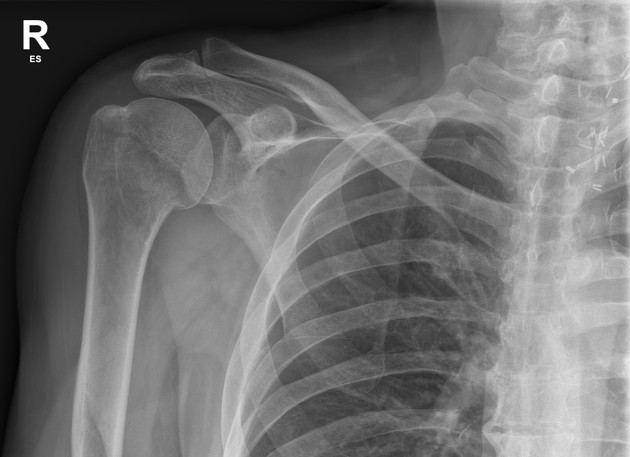

causes of shoulder dislocation

weakness of rotator cuff tendons and tendonitis, or trauma

head of humerus subluxes from glenoid cavity

usually when humerus is in abduction or flexion

occurs in the inferior direction and aspect

weakest region of capsule

humerus pulled either anterior/posterior to shoulder joint upon which rotator cuff muscles are injured

arm hangs limp at prominent “step deformity” space between acromion and humeral head